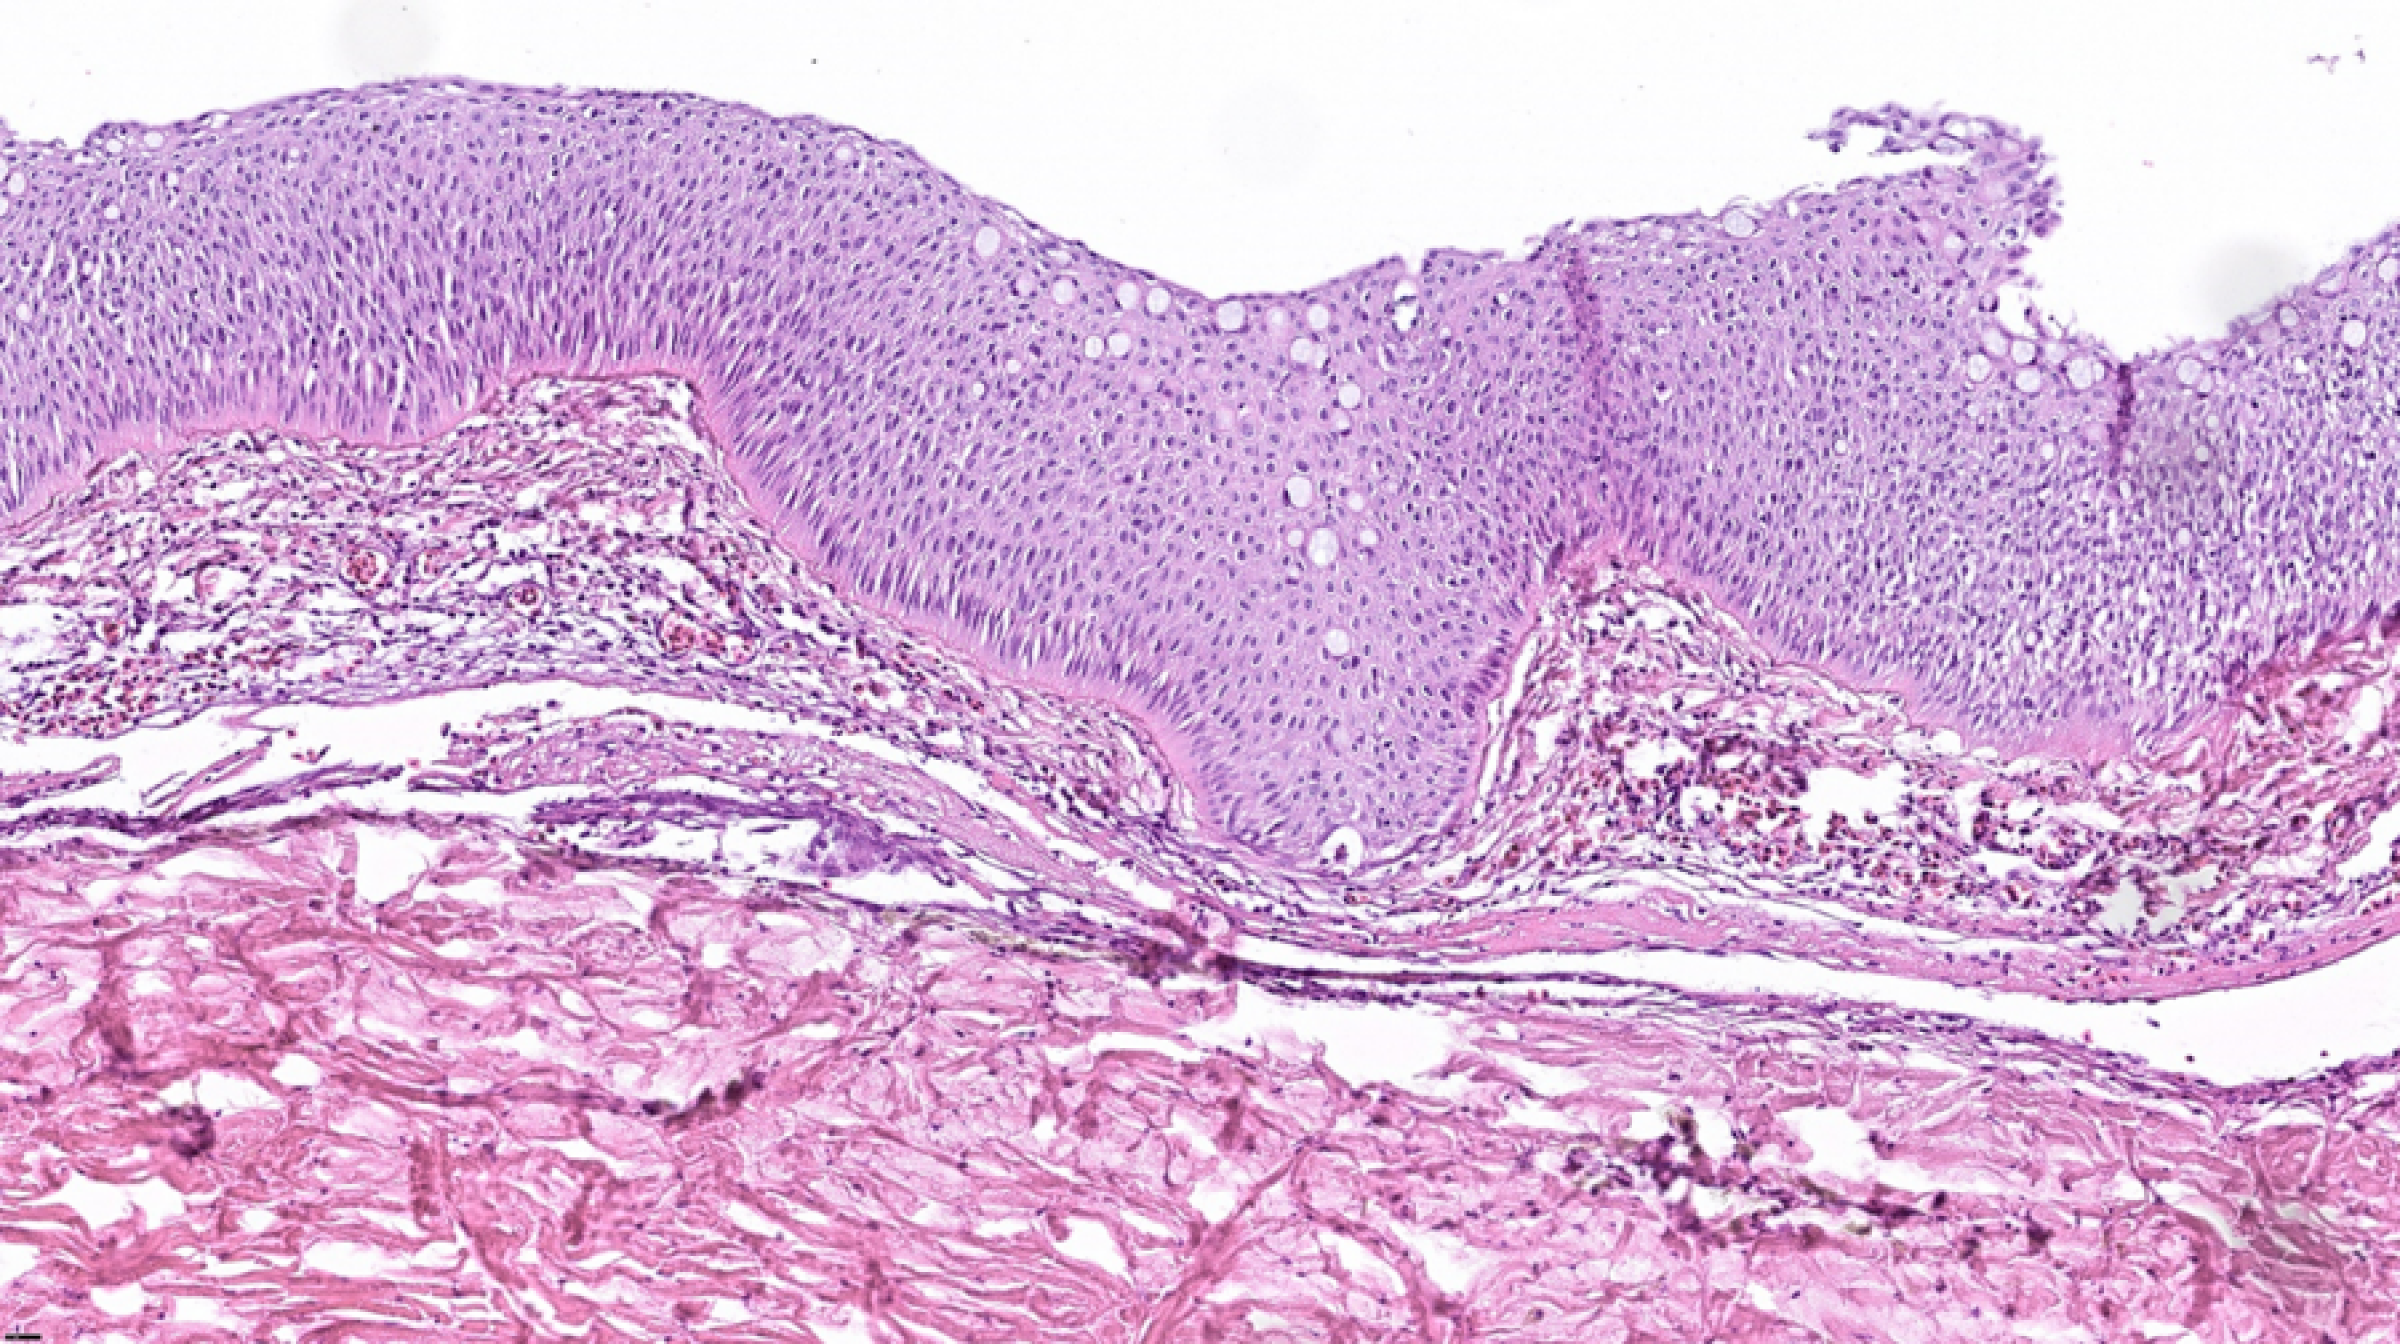

Videre karakteriseres patologiske forandringer ved mikroskopi av vevssnitt (histopatologi) da det gir ledetråder med hensyn til hva slags type sykdom en står overfor: Noen ganger er det svært karakteristiske funn ved spesielle sykdommer.

I helt nygått laks fra Enningsdalselva var hudskadene preget av tap av skjell og ytterste hudlaget (epidermis) sentralt, mens det i ytterkant var intakt epidermis underminert av blødning rett under – men ikke dypere (Figur 1). Senere i forløpet fant man mer omfattende sår infisert med sopphyfer og en betennelsesreaksjon, mest trolig en konsekvens av skadet hudbarriere.